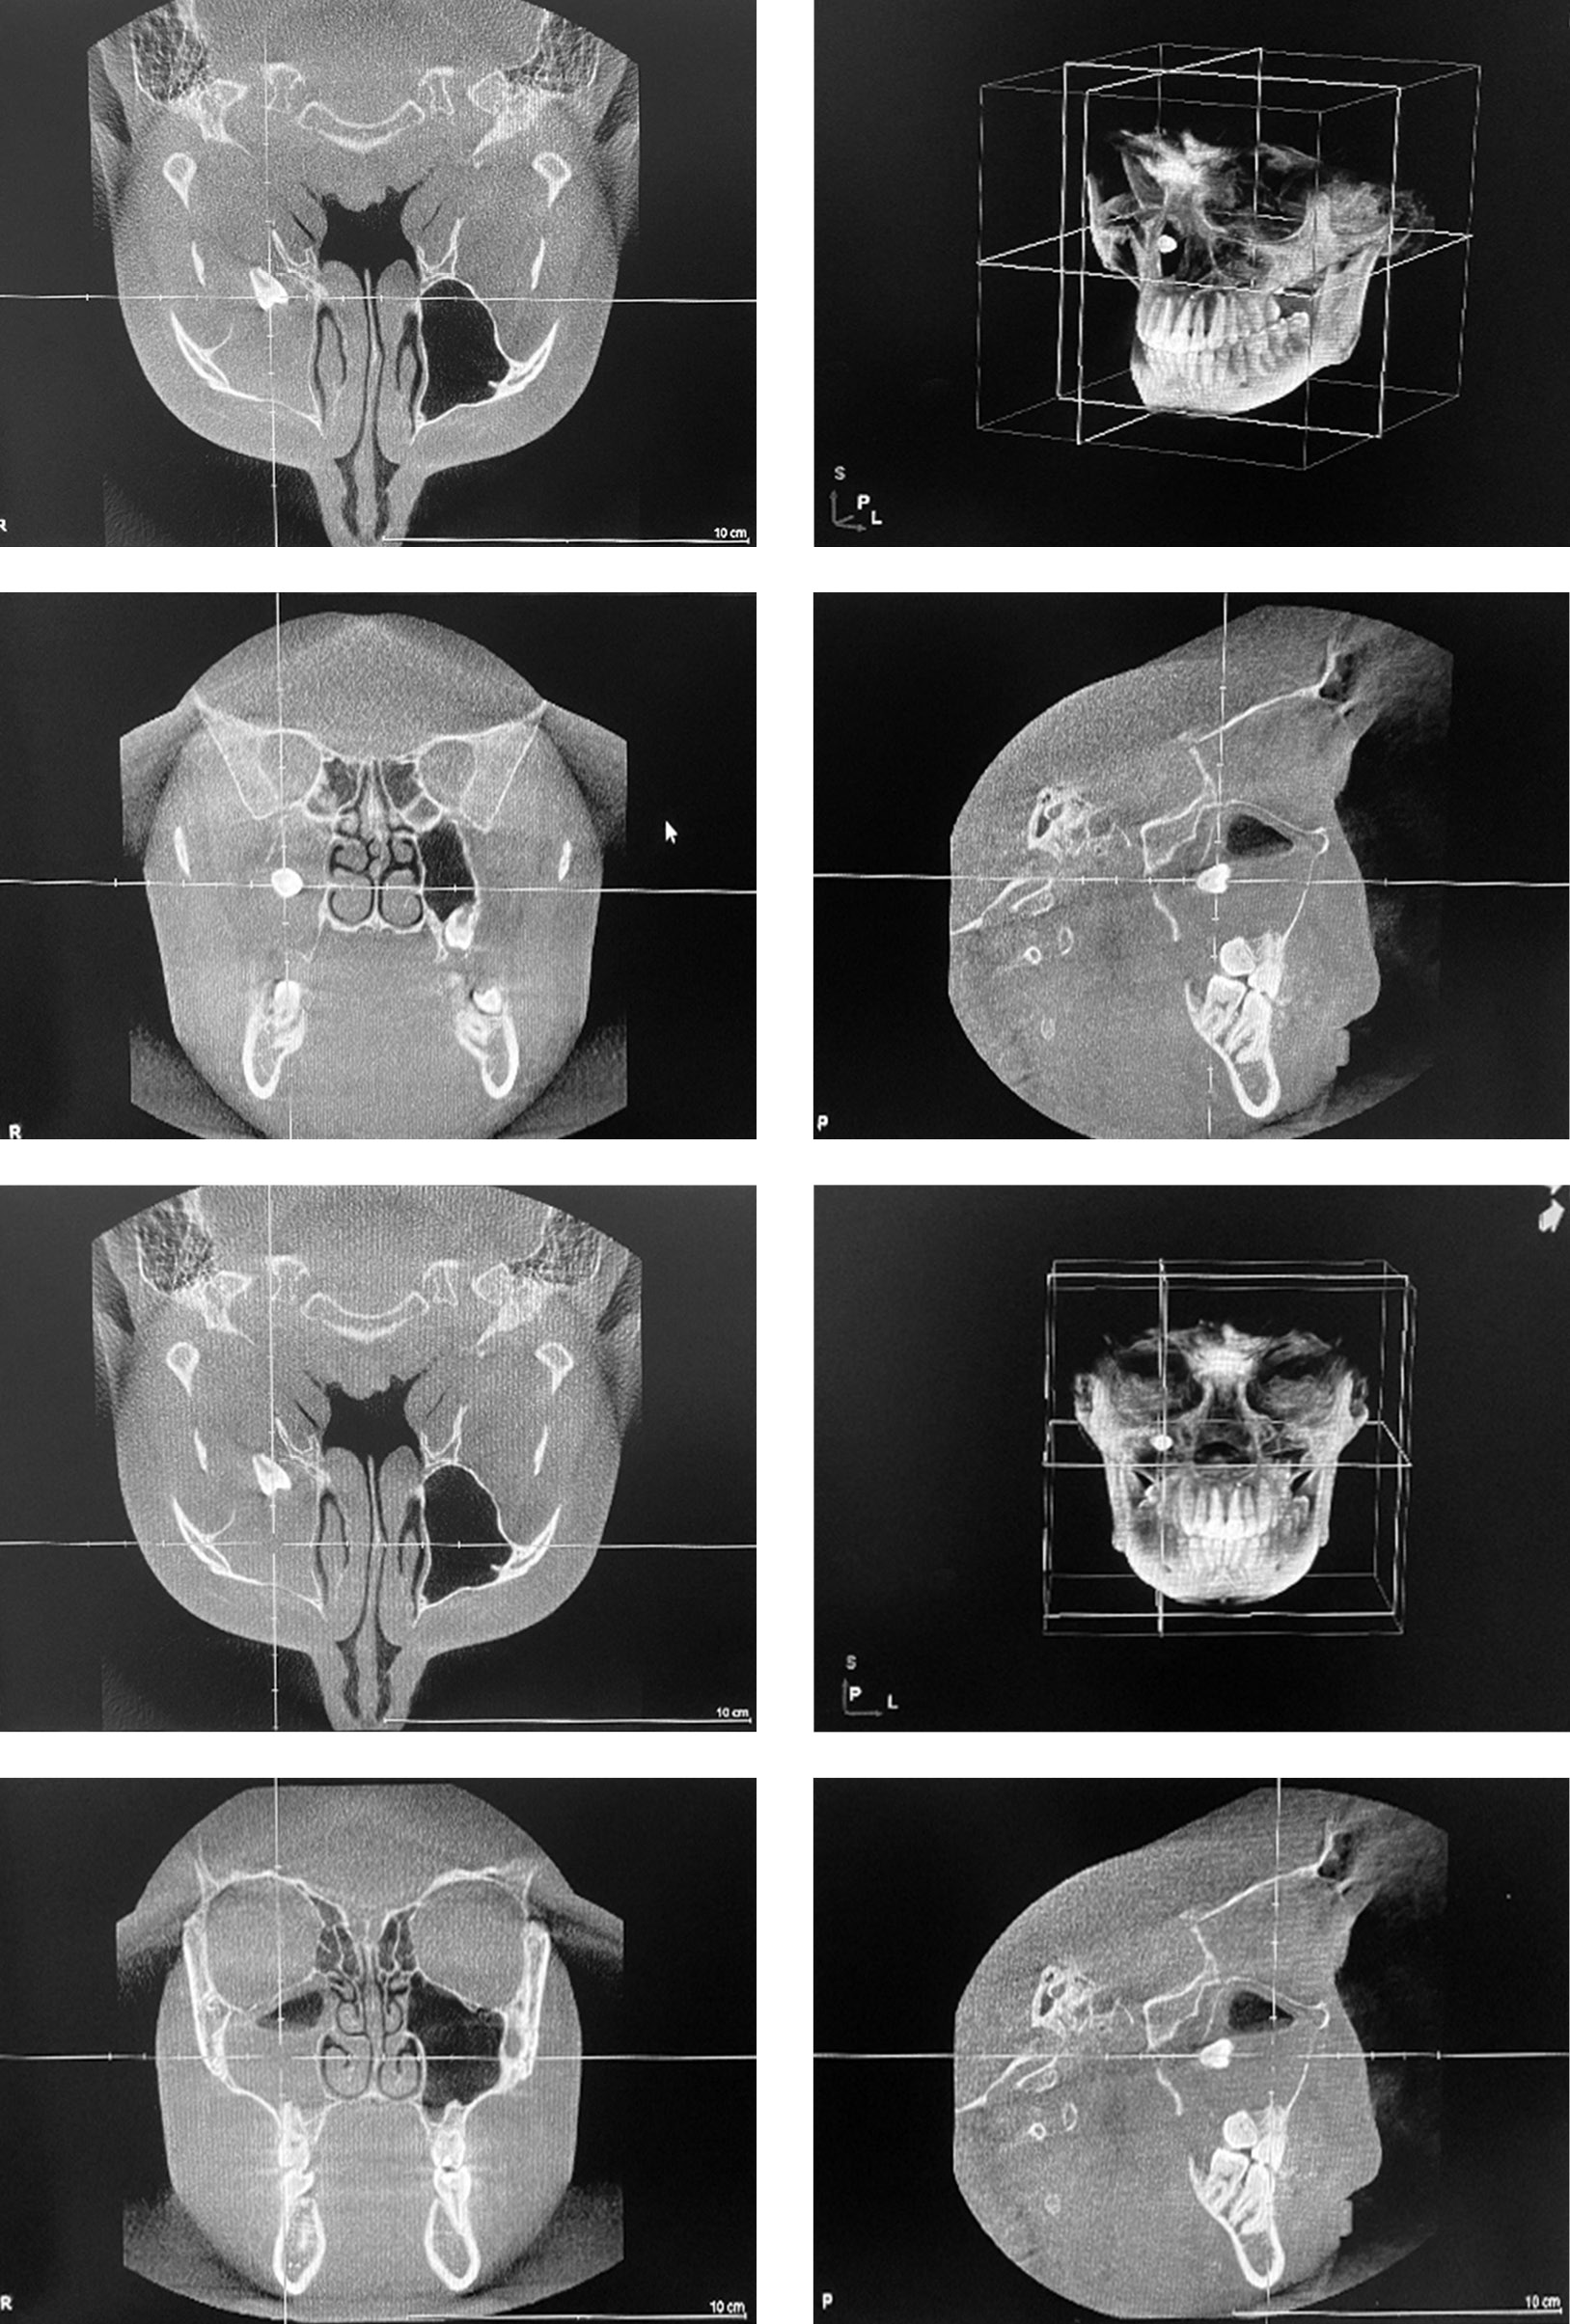

Patient C, 20 years old, was urgently admitted to the Clinic of Oral Surgery of the First Pavlov State Medical University of St. Petersburg with complaints of nasal congestion, more severe on the right side, mucopurulent posterior pharyngeal discharge, pain in the right cheek and cheekbone. Cone beam computed tomography showed subtotal shadowing of the right maxillary sinus with exudate component, defect in the posterior wall of the right maxillary sinus, diverted tooth 1.8 (Figure 1). A puncture of the right maxillary sinus provided a moderate amount of purulent discharge with a foul odor. The decision was made to perform a right maxillary antrostomy. Under general anesthesia, a linear incision was made in the oral mucosa along the upper fornix of the vestibule at the level of tooth 1.4 to create an antrostomy opening with a cutter after the detachment of the mucoperiosteal flap. The cyst capsule was visualized. A cyst and a diverted tooth 1.8 were removed, and the sinus was curretted. Under the guidance of a 0° rigid endoscope, the right maxillary sinus was opened via an infraturbinal approach and the identified granulation and polypous tissues were removed. The sinus was examined using 45° and 70° endoscopes. Sinus and nasal cavity tamponade was performed. In the postoperative period, the patient received systemic antibacterial, decongestant, and analgesic therapies. Follow-up cone beam computed tomography 1 month after the surgery showed complete restoration of maxillary sinus airness and absence of foreign body.

Fig. 1. Cone beam computed tomography: subtotal shadowing of the right maxillary sinus with exudative component, defect in the posterior wall of the right maxillary sinus, diverted tooth 1.8

Рис. 1. Конусно-лучевая компьютерная томография: субтотальное затенение правой верхнечелюстной пазухи с наличием экссудативного компонента, дефект задней стенки правой верхнечелюстной пазухи, ретинированный зуб 1.8